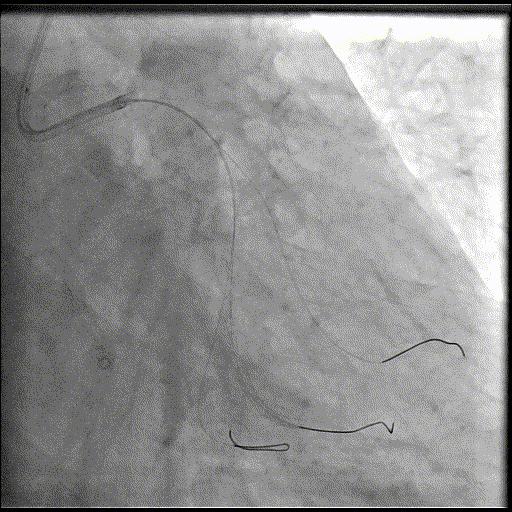

手术过程

导丝到位

当指引导管冠脉开口到位后,选择三根对应导丝分别送入LCX、OM1、OM2远端。

OM2优先处理:

球囊预扩

当导丝通过病变后其他器械无法通过病变,此时选择不同尺寸的小球囊逐级预扩张病变,复查造影狭窄减轻不明显。为了解血管真实情况,遂启用IVUS检查。

术前腔内影像学IVUS指导

IVUS提示血管可见钙化明显,为360°环形钙化。遂考虑启动IVL治疗。

冲击波球囊治疗

2.5*12mm@4atm 冠脉血管内冲击波导管反复进行4个周期治疗,复查造影提示狭窄减轻。

支架植入并后扩

于OM2-LCX远端植入一枚药物洗脱支架,经非顺应性球囊后扩张支架,复查造影提示支架贴壁良好,未见夹层、血肿。